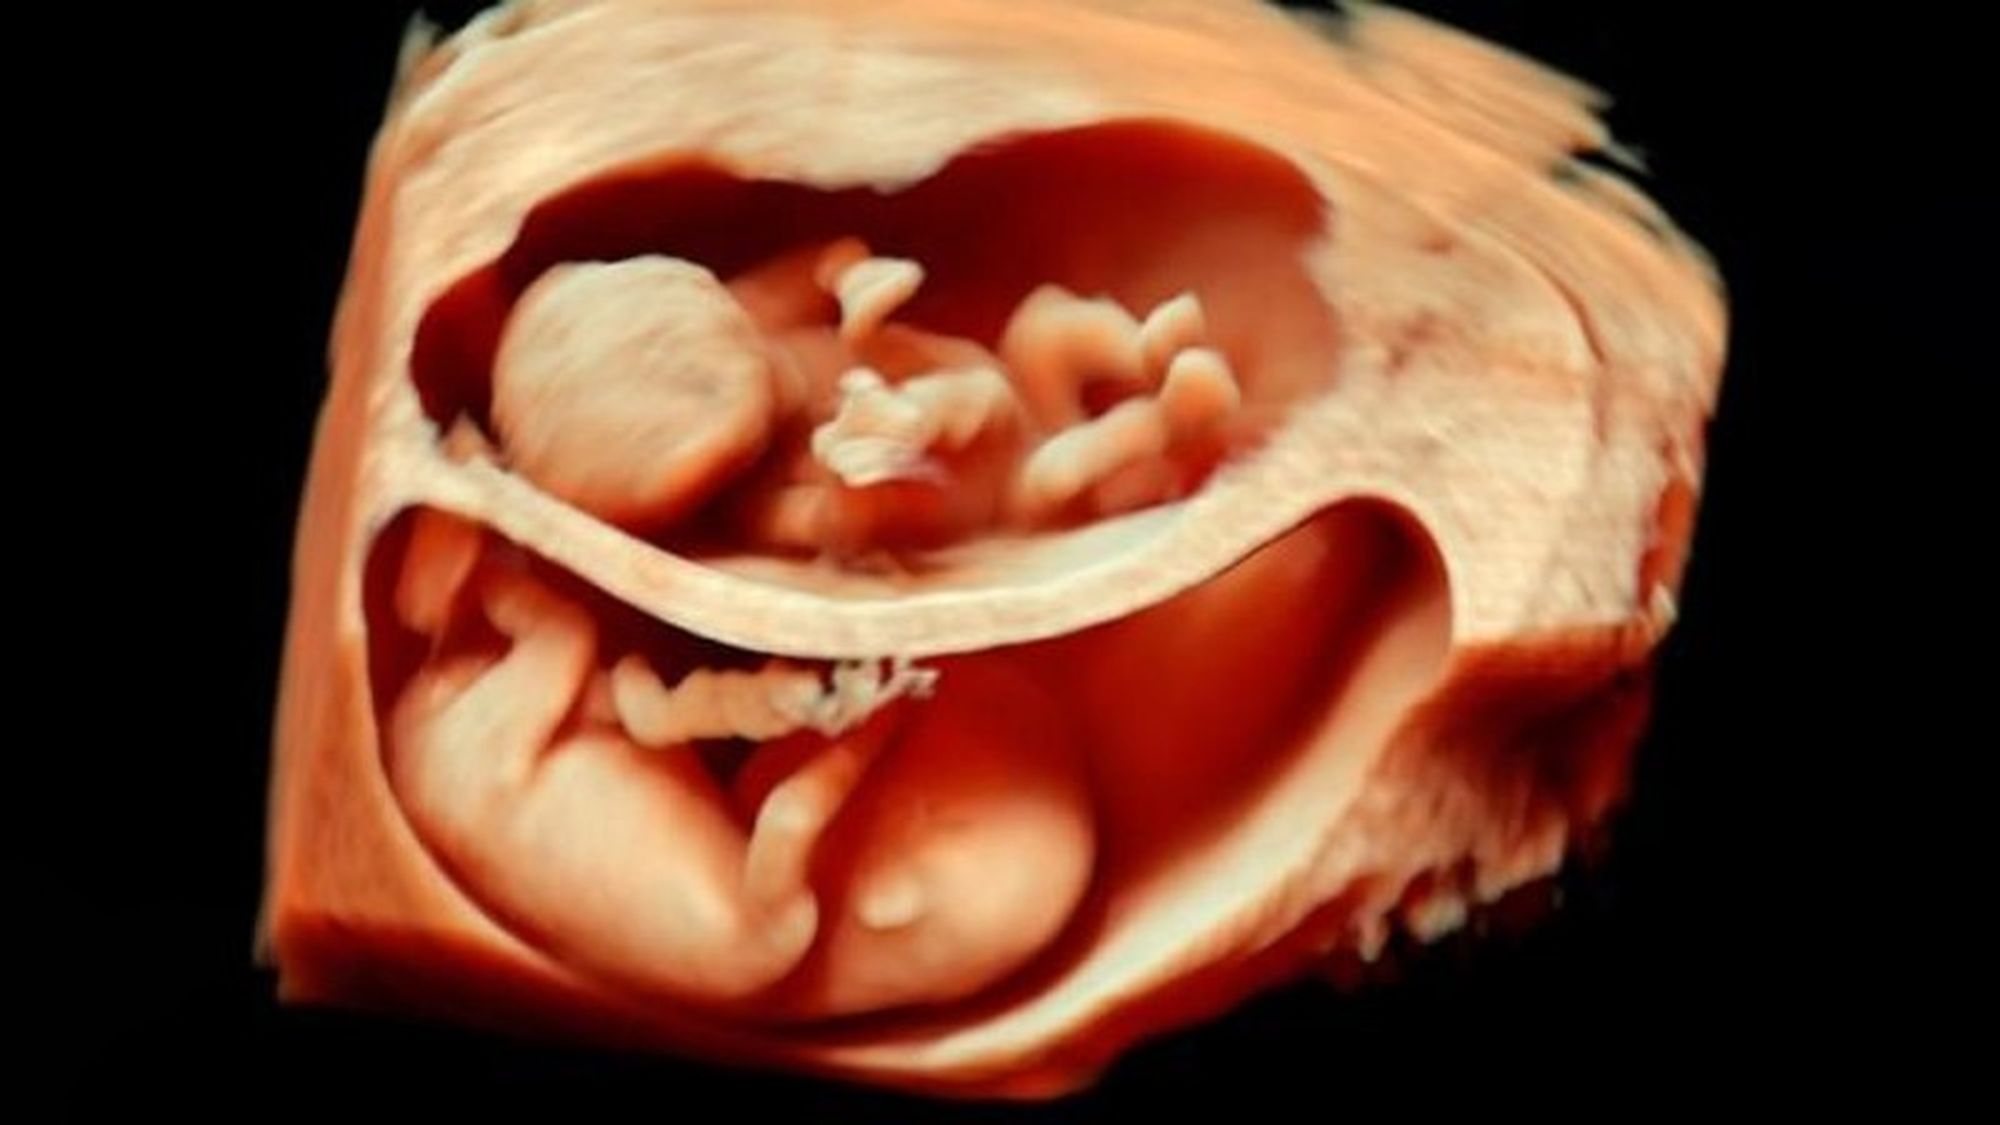

Bu görüntüleme tekniği sayesinde, artık renkli ve çok daha net sonuçlara ulaşabiliyoruz. Bu görseller, bunun en net ispatlarından biri. Ana karnındaki ikizleri çok detaylı bir şekilde görüntülemek artık mümkün. Hem de o, uzaktan odaklanılmış bir kare. Aşağıdakiler, ne demek istediğimizi daha net anlatacaktır:

3D ultrasonlarda, birden fazla açıdan 2 boyutlu görüntüler çekiliyor ve sonrasında bilgisayar yardımıyla 3 boyutlu bir görsele dönüştürülüyor. Bu sayede bebeğinizin sadece bir kesidini değil, 3 boyutlu bir görüntüsünü elde etmeniz mümkün oluyor.

4D ultrasonlarda ise, 3D olan görüntüler zamana yayılmış bir şekilde kaydediliyor. Bu sayede bebeğin hareketlerini tıpkı bir video izler gibi görmeniz mümkün oluyor. Bu sayede bebeğin gözlerini açıp kapaması, gülümsemesi veya parmağını emmesi gibi olayları çok net bir şekilde görüntüleyebiliyorsunuz.